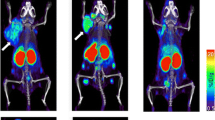

To overcome the long circulating half-life of mAbs, smaller molecules can be used and they include peptides or small proteins like cytokines. In particular, radiolabelled IL2 is one of the most studied cytokine-based radiopharmaceuticals. Its receptor, the CD25, is overexpressed on activated T lymphocytes and it drives their proliferation and inflammatory response. Therefore, radioactive IL-2 as a radiopharmaceutical to target T cells in vivo has been pioneered by Signore et al. in many autoimmune pathologies. A recent study, conducted in patients affected by metastatic melanoma and undergoing immunotherapy with either pembrolizumab or ipilimumab, demonstrated the feasibility of its use as a candidate-imaging tool to evaluate TILs into tumors [162]. Indeed, in some patients, lesions with high SUV at the pre-therapy scan positively responded to the therapy. However, what emerged from this study is that intra-patient heterogeneity is a true open challenge, since in the same patient, differential uptake in studied lesions over the course of the therapy were observed (Fig. 2). This leads to the need of more accurate studies in a higher cohort of patients, to understand common patterns of uptake and understand the mechanisms that cause therapy response or failure. As an alternative to intact mAbs, radiolabelled fragments like diabodies or minibodies offers a lower half-life (2-5 h or 5-12 h respectively) with faster clearance from the blood pool. However, lower specificity and stability is a common issue that should be taken into account.